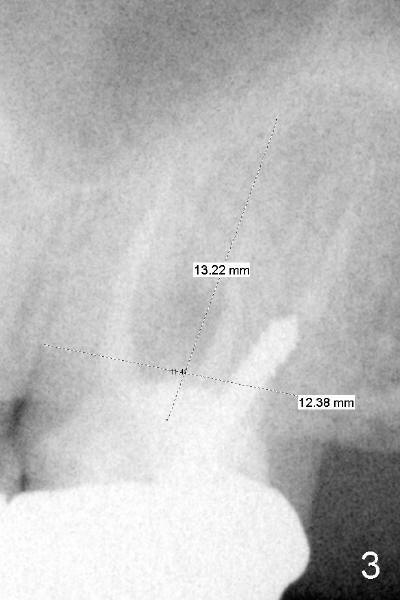

A 42-year-old lady has had problems with the tooth #15 for 4 years. First the crown was dislodged with open margin and furcal lesion (> in Fig.1, P: post; X-ray taken in 2008). Since 2009 (Fig.2,3), the tooth has occasional swelling. The furcal radiolucency remained in the panoramic X-ray (Fig.4 and 4'). Now the patient agrees to have extraction and implant placement.